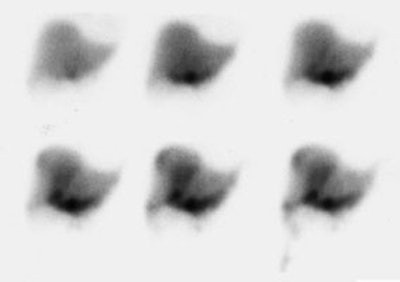

Bile Leak: The post-cholecystectomy patient shown below was being evaluated for abdominal pain and fever. The CT scan demonstrated a fluid collection anterior to the liver (white arrows- click CT image to enlarge). A hepatobiliary study demonstrated a bile leak. Increasing tracer activity can be seen over the liver corresponding to the fluid collection on the CT scan. Bile can also be seen pooling in the gallbladder fossa and extending down the right paracolic gutter. |